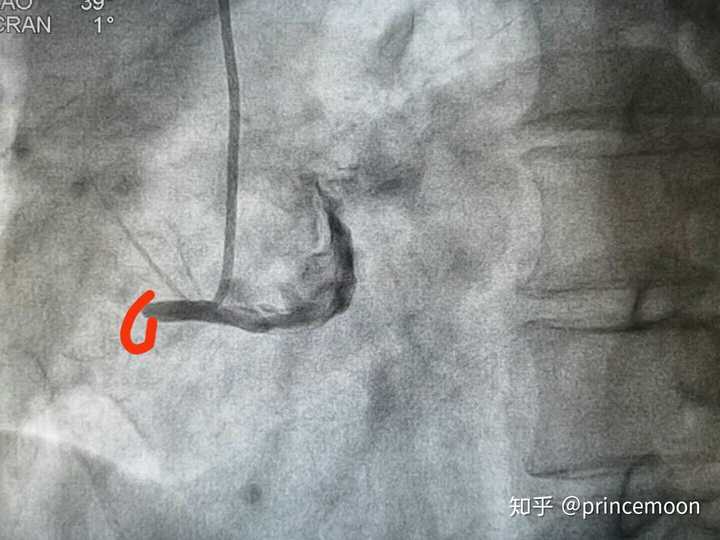

心脏前间壁在哪图片,心脏前壁和前间壁实图

心肌梗死按发生的部位可分为 下壁,右室,前壁,前间壁,后壁等类型.

心脏前壁和前间壁实图

前间壁心梗心电图图片

心脏前间壁

前间壁心梗心电图表现

前间壁心梗心电图